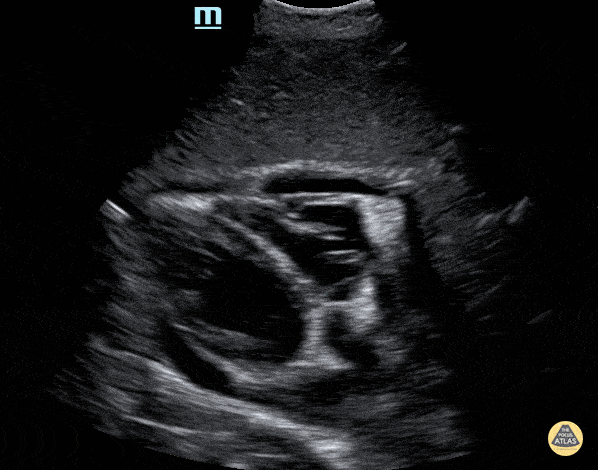

Small pericardial effusion in the subxiphoid view. Contributor: Peter Gutierrez, MD, FAAP, Emory University School of Medicine/Children's Healthcare of Atlanta, @pocuspete